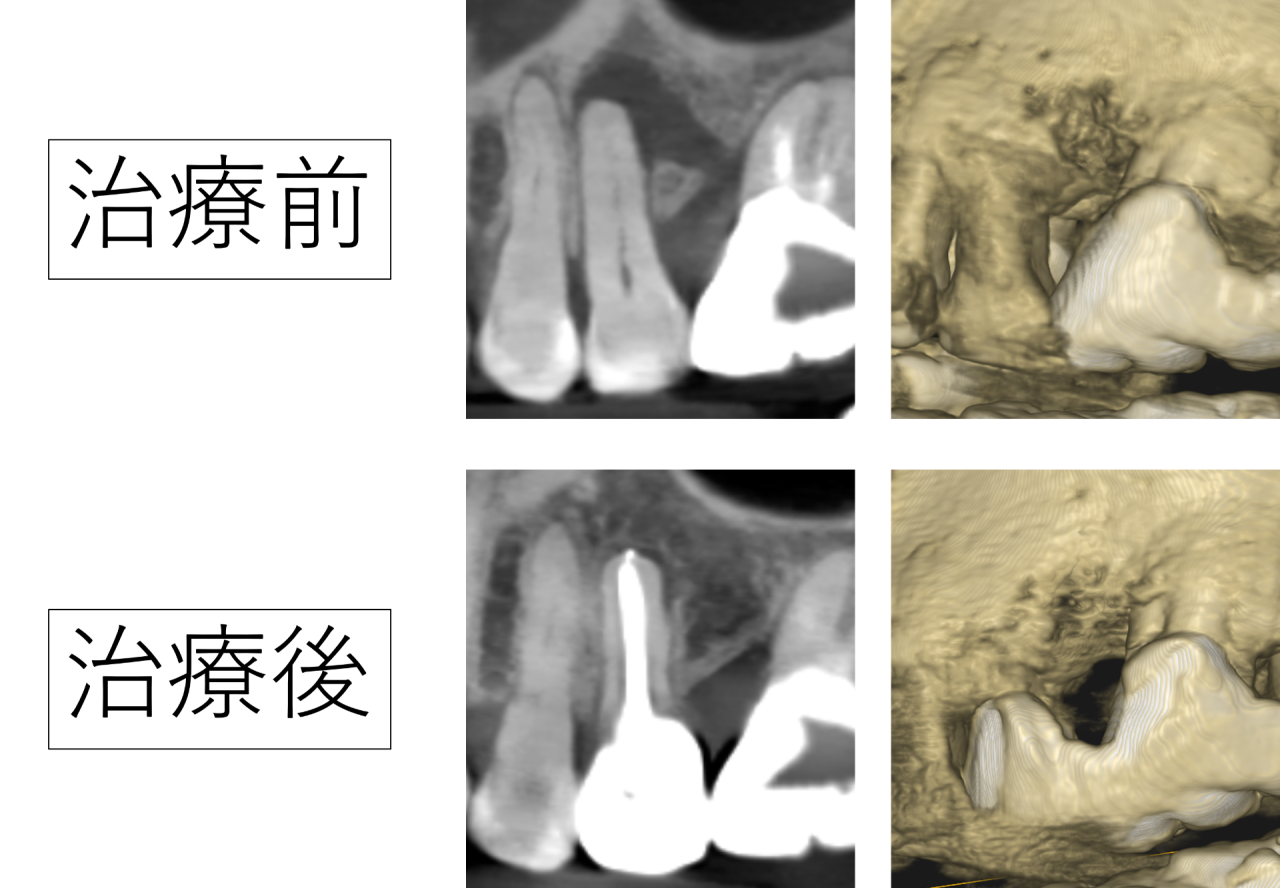

根管治療後、定期的に経過を確認しました。

治療前に大きく写っていた黒い影は、時間の経過とともに小さくなり、骨の回復が確認できました。